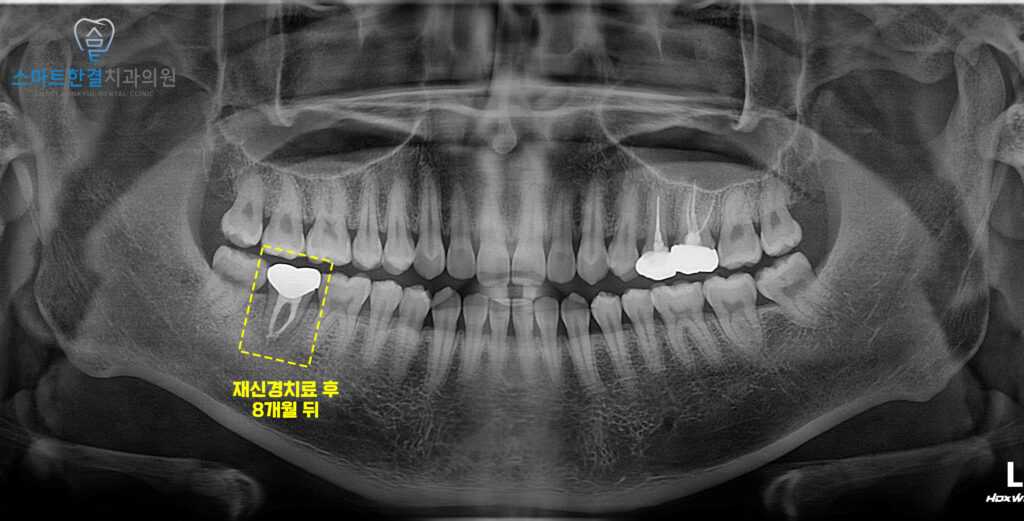

이렇게 치료가 마무리된 후

8개월 뒤 내원하셨을 때

불편감 없이 잘 사용하고 계셨어요.

치료를 마무리한 이후에는

정기적인 경과 확인을 위해

지속적으로 내원해 주셨는데요.